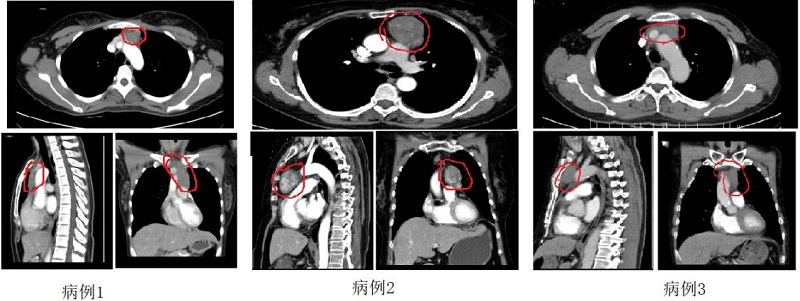

病例1 陈某因肌无力就诊神经外科,入院检查后发现纵隔肿瘤,肿瘤与无名静脉关系紧密,侧切口手术视野受限,手术风险增大,采用剑突下入路行胸腺肿瘤及周围脂肪组织完整切除术,术后5天顺利出院。

病例2张某因胸闷气喘行CT检查发现有胸腺瘤,肿瘤包饶左无名静脉,经剑突下胸腔镜胸腺扩大切除术,术后第3天康复出院。

病例3成某体检发现胸腺瘤,增强CT显示前上纵隔不规则轻度强化软组织灶,病灶内多发沙粒状钙化,与左侧头臂静脉分界不清,上纵隔淋巴结略肿大,多考虑恶性病变,行剑突下入路胸腔镜下纵隔肿瘤切除术,术后3天顺利出院。